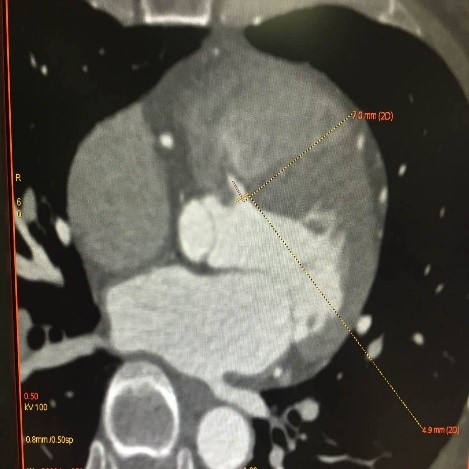

在室间隔缺损的患者中,行介入封堵术常常需要用猪尾导管行左室造影,以确定室间隔缺损的形态、大小和缺损上缘距主动脉右冠瓣的距离。另需要依据造影测量的缺损直径选择封堵器的规格,封堵器释放过程中需要通过术者手感、透视和超声,甚至心室造影确定封堵器的位置,以确保无残余分流。 GE 心脏高级解决方案可依据患者术前 CT 重建心脏3D解剖结构,术前可测量缺损直径和规划缺损路径,术中实时引导封堵手术,提高手术精度。 具体操作步骤如下: 术前规划:DSA直接处理CT数据

a、一键提取心室和心房3D模型 b、测量缺损上缘距主动脉右冠瓣的距离

c、规划室间隔缺损位置,为术中实时引导释放封堵器进行标记和提示